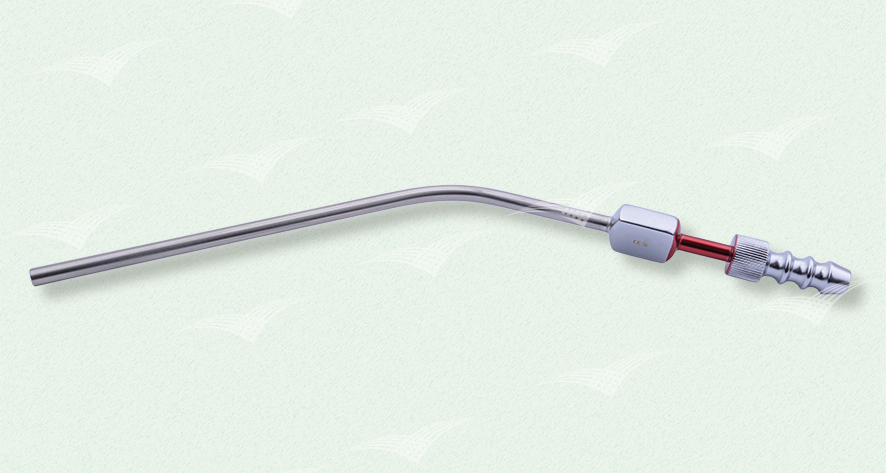

Frazier Sauger

einzeln steril verpackt, Einweg Metallinstrument

Artikelnummer: n. v.

Kategorien: Einweg-Produkte, Metallinstrument